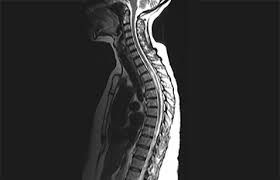

Jan 14, 2017 · transverse myelitis is an inflammatory condition of the spinal cord associated with rapidly progressive neurologic dysfunction. The av shunt is located inside the dura mater close to the spinal nerve root where the arterial blood from a. In the acute setting, there is often associated contrast enhancement. G37.3 acute transverse myelitis in demyelinating disease of central nervous system g37.4 subacute necrotizing myelitis of central nervous system g37.5 concentric sclerosis balo of central nervous system g37.8 other specified demyelinating diseases of central nervous system g37.9 demyelinating disease of central nervous system, unspecified Transverse myelitis postsurgical spine avm brachial plexus post radiation therapy, eval for mass lesions, entrapment, denervation cervical spine w and w/o contrast 72156 thoracic disc disease pain radiculopathy trauma thoracic spine w/o contrast 72146 tumor infection ms syrinx transverse myelitis postsurgical spine avm Compression of the upper spinal cord, multiple sclerosis, transverse myelitis, behçet's disease, osteogenesis imperfecta lhermitte phenomenon , also called the barber chair phenomenon , is an uncomfortable electrical sensation that runs through the back and into the limbs. They most commonly affect elderly men and are classically found in the thoracolumbar region. Rare neurological complications include transverse myelitis and/or cauda equina syndrome 20, 21; As part of a health sciences university, baylor medicine in houston, texas puts the latest treatments, innovations, and therapies in the hands of its highly trained doctors and care teams, who are working together to develop and deliver a care plan personalized for you.

Compression of the upper spinal cord, multiple sclerosis, transverse myelitis, behçet's disease, osteogenesis imperfecta lhermitte phenomenon , also called the barber chair phenomenon , is an uncomfortable electrical sensation that runs through the back and into the limbs. G37.3 acute transverse myelitis in demyelinating disease of central nervous system g37.4 subacute necrotizing myelitis of central nervous system g37.5 concentric sclerosis balo of central nervous system g37.8 other specified demyelinating diseases of central nervous system g37.9 demyelinating disease of central nervous system, unspecified Transverse myelitis postsurgical spine avm brachial plexus post radiation therapy, eval for mass lesions, entrapment, denervation cervical spine w and w/o contrast 72156 thoracic disc disease pain radiculopathy trauma thoracic spine w/o contrast 72146 tumor infection ms syrinx transverse myelitis postsurgical spine avm Jan 14, 2017 · transverse myelitis is an inflammatory condition of the spinal cord associated with rapidly progressive neurologic dysfunction. The av shunt is located inside the dura mater close to the spinal nerve root where the arterial blood from a.